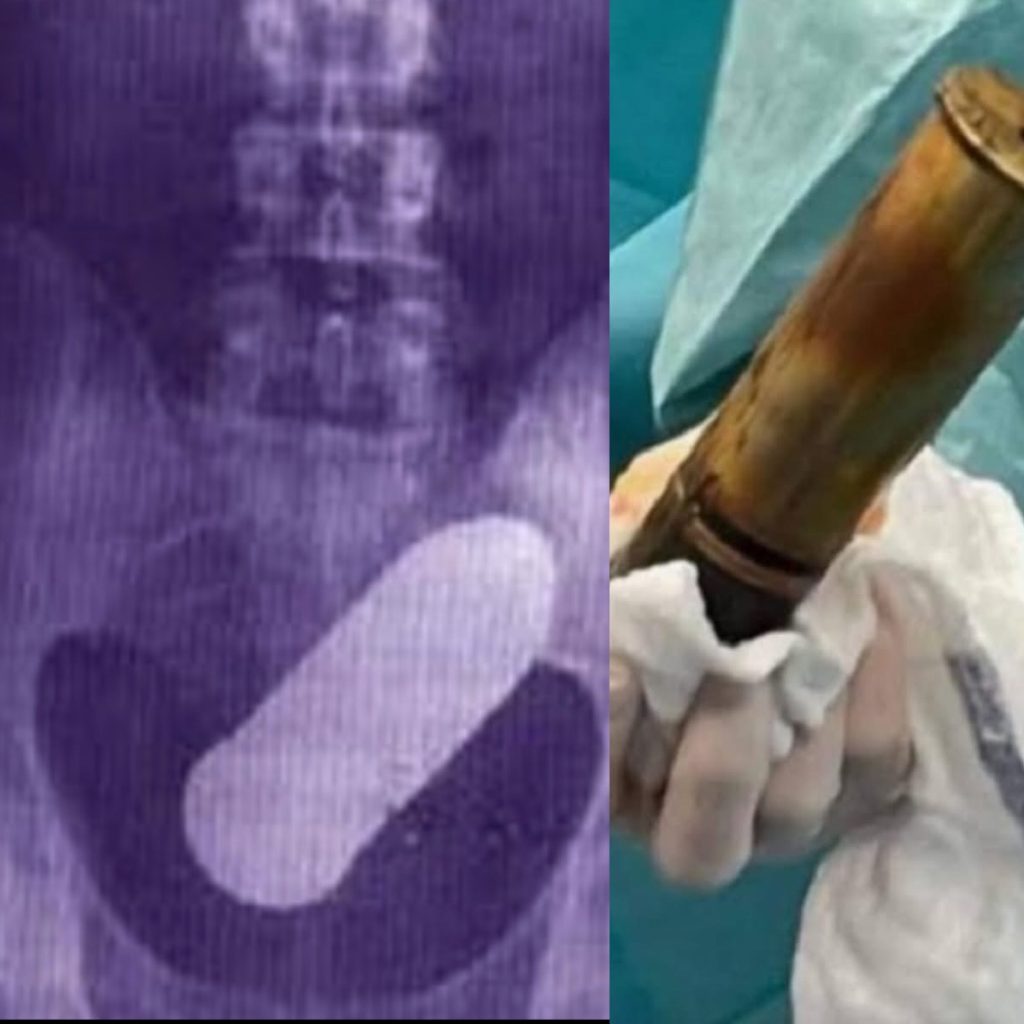

Tânărul s-a prezentat la Camera de Gardă a Spitalului Rangueil cu dureri severe, iar radiografia a arătat un obuz de aproximativ 20 cm blocat în corp. Descoperirea a determinat personalul să anunțe experți în dezamorsare, pompieri și forțele de ordine, iar întregul spital a fost evacuat din motive de siguranță.

Chirurgii au efectuat o operație de urgență pentru extragerea obuzului, care nu era explodat, iar ulterior acesta a fost neutralizat de echipele specializate. Autoritățile analizează deschiderea unui dosar penal împotriva pacientului pentru manipularea de muniții periculoase.